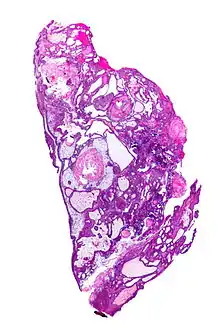

On macroscopic examination, craniopharyngiomas are cystic or partially cystic with solid areas. On light microscopy, the cysts are seen to be lined by stratified squamous epithelium. Keratin pearls may also be seen. The cysts are usually filled with a yellow, viscous fluid rich in cholesterol crystals. Of a long list of possible symptoms, the most common presentations include headaches, growth failure, and bitemporal hemianopsia.

Micrograph showing a papillary craniopharyngioma, HPS stain